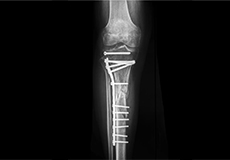

Knee Fracture Surgery

A knee fracture is a broken bone or a crack in or around the joint of the knee. This can involve the tibia (shin bone), the kneecap (patella), or femur (thighbone) where they connect with the knee.

Fractures of the Tibia

The lower leg is made up of two long bones called the tibia and fibula that extend between the knee and ankle. The tibia or shinbone is the larger of the two bones. It bears most of the body’s weight and helps form the ankle joint and knee joint.